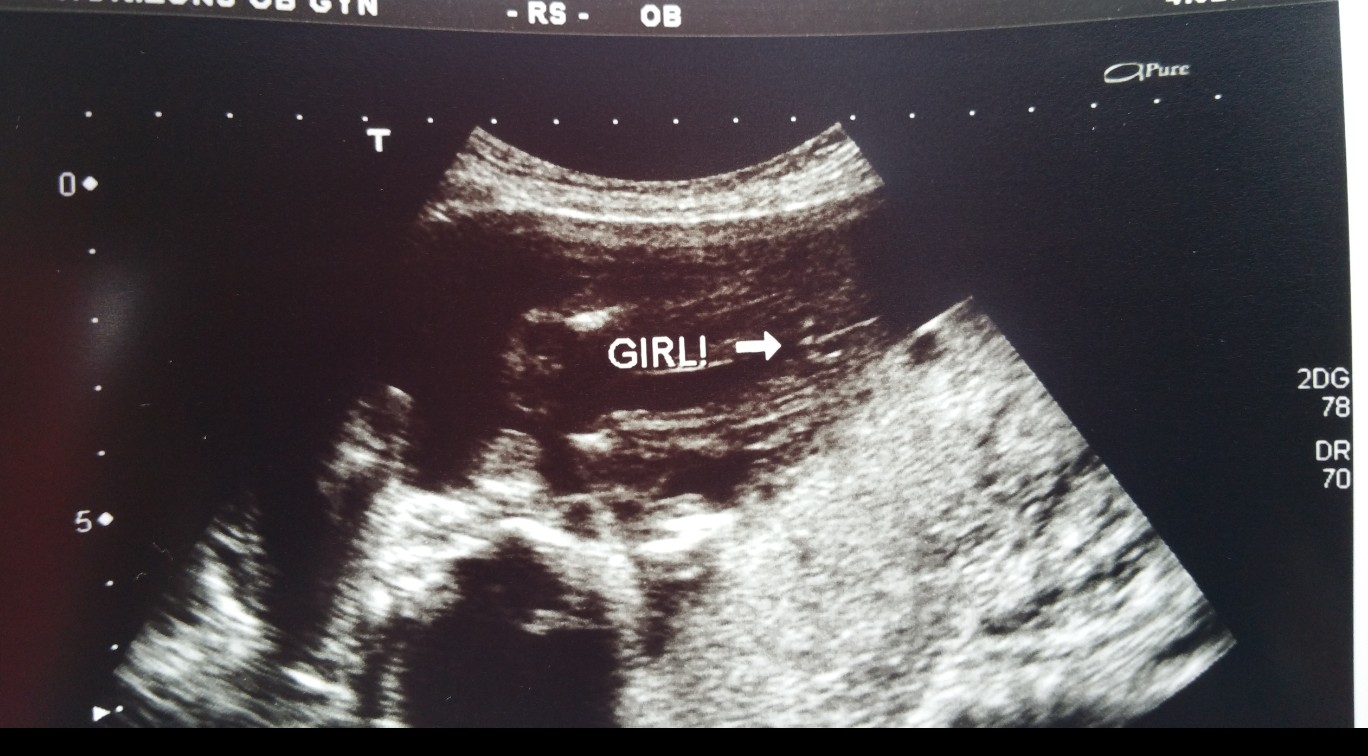

Hello ladies, I am new here but hoping I could have some opinions. I got a gender ultrasound at 20 weeks and doc is leaning towards girl, but the lines are rounded except for the one down the middle. Baby would not open their legs so it was tough I go for another soon, but I'm just wondering what you all think. Thanks!! :)

• I don't really know anything, but... I thought it was 2 lines for a boy and 3 lines for a girl. So my guess would be girl! x

• Ya its a tough call. My first doctor told me boy at 15 weeks when baby was spread eagle and then this doctor told me girl.

• I'm not sure how to read the sonograms. I've just gotten lucky when figuring out that my son was a boy when I saw the images and then the tech or doctor confirmed it for me and explained it. My best suggestion would be to wait until your next sonogram and tell your doc or tech your questions and/or confusions. I'm sure they'd explain it better than me, but I agree with the guess that it looks like a girl.